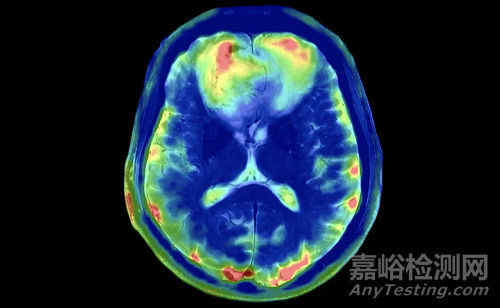

磁共振成像系統(tǒng)由7T超導(dǎo)磁體、梯度系統(tǒng)、射頻系統(tǒng)、射頻線圈、工作站、生理信號(hào)門控系統(tǒng)、檢查床、電子柜組成,主要用于臨床核磁共振成像診斷。

該產(chǎn)品采用深度學(xué)習(xí)技術(shù),在7T高場(chǎng)磁共振成像系統(tǒng)基礎(chǔ)上增加了靜動(dòng)態(tài)多通道發(fā)射平臺(tái)與多核成像功能,可提供頭部鈉圖像、四肢肌肉和肝臟的磷核波譜數(shù)據(jù)。該產(chǎn)品利用多通道與多核成像優(yōu)勢(shì),實(shí)現(xiàn)圖像的實(shí)時(shí)調(diào)節(jié),可有效提高以中樞神經(jīng)系統(tǒng)疾病為主的影像診斷效能,提高相應(yīng)疾病治療水平。

在神經(jīng)影像學(xué)中,7T MRI的信噪比(SNR)比3T提升近兩倍,使亞毫米級(jí)成像成為可能,可清晰分辨海馬結(jié)構(gòu)、灰質(zhì)層次與腦干細(xì)節(jié),為阿爾茨海默病、多發(fā)性硬化、癲癇灶點(diǎn)的早期檢測(cè)提供了“形態(tài)解剖之外的證據(jù)”。

7T系統(tǒng)亦首次實(shí)用化了多核成像能力(Multinuclear Imaging),可檢測(cè)鈉核(Na-23)與磷核(P-31)信號(hào),用于評(píng)估腦代謝異常、肌肉能量代謝或肝臟磷代謝異常,逐步向“結(jié)構(gòu)+功能+代謝”的三維融合過(guò)渡。